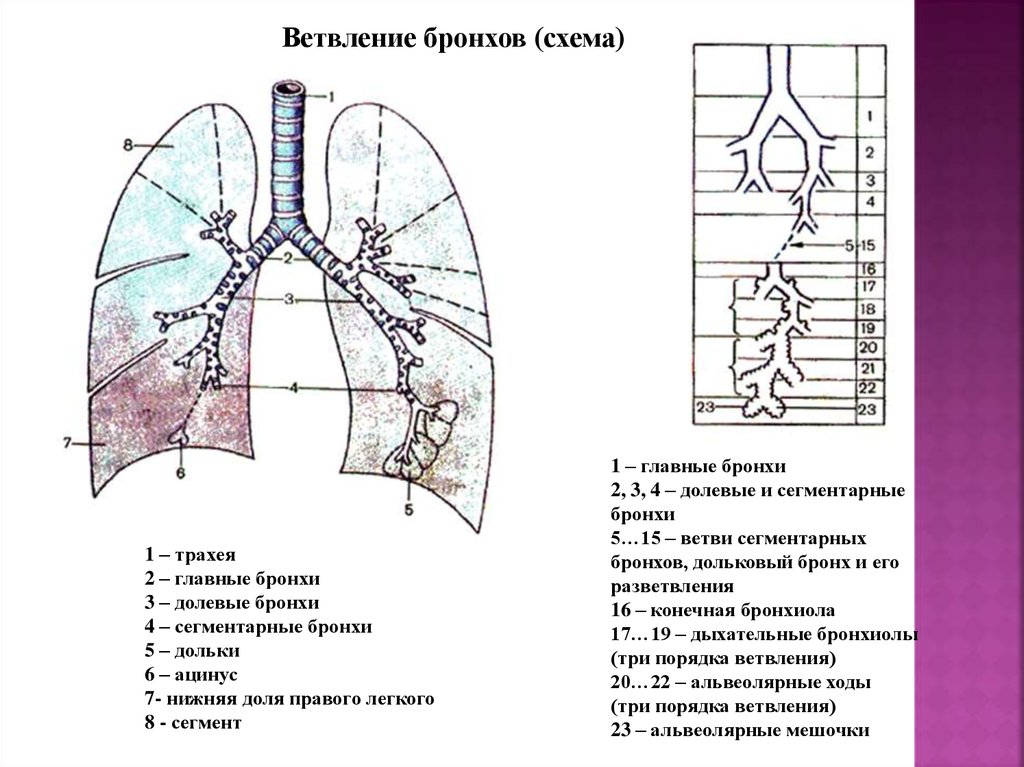

Анатомические изображения сегментов легких различных животных

Раздел: Другие животные